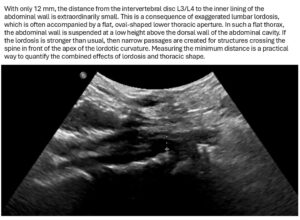

- Exaggerated lumbar lordosis

- Low-grade compression of the vena cava at its root in front of the intervertebral disc L3/L4